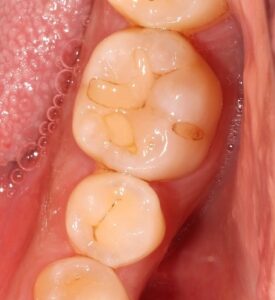

お口の中を見てみると、

すごく黒くなっていますね・・・(*_*)

上の奥歯はご自身では見えませんし、

さらに頬っぺた側は、頬っぺたが邪魔をして自分では見えづらい場所となります。

また歯ブラシも意識して磨かなければ磨けないところです。

汚れが残り、虫歯が徐々に進行していきます。

表面から削っていっている途中ですが、

内部まで黒く虫歯が侵入しています。

左側、頬っぺたがぶつかっている所が黒く虫歯になっており、

内部入り込んでいます。

歯の半分くらい削っています。